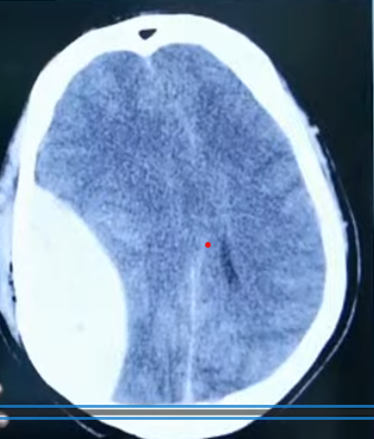

Q7. Identify the condition shown in CT

- EDH

- SDH

- SAH

- ICH

Answer – A